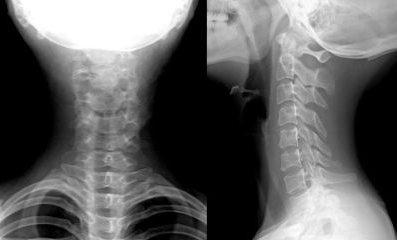

【医生检查】 CT显示颈椎间盘退变,颈椎4、6突出,及症状检查

【医生诊断】 颈椎间盘突出